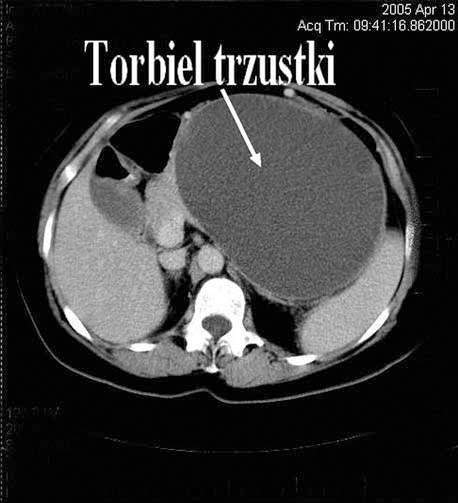

KT – obraz torbieli przy pierwszym przyjęciu do szpitala

Kilkuletnia obserwacja zropiałej torbieli trzustki, która ostatecznie okazała się nowotworem – opis przypadku

W pracy opisano przypadek 48-letniej chorej z olbrzymią zropiałą torbielą trzustki, u której po 4 latach stwierdzono cechy złośliwego procesu nowotworowego.